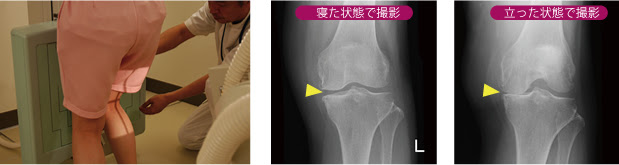

膝のレントゲン画像からわかる変形性膝関節症のkl分類について 足立慶友整形外科